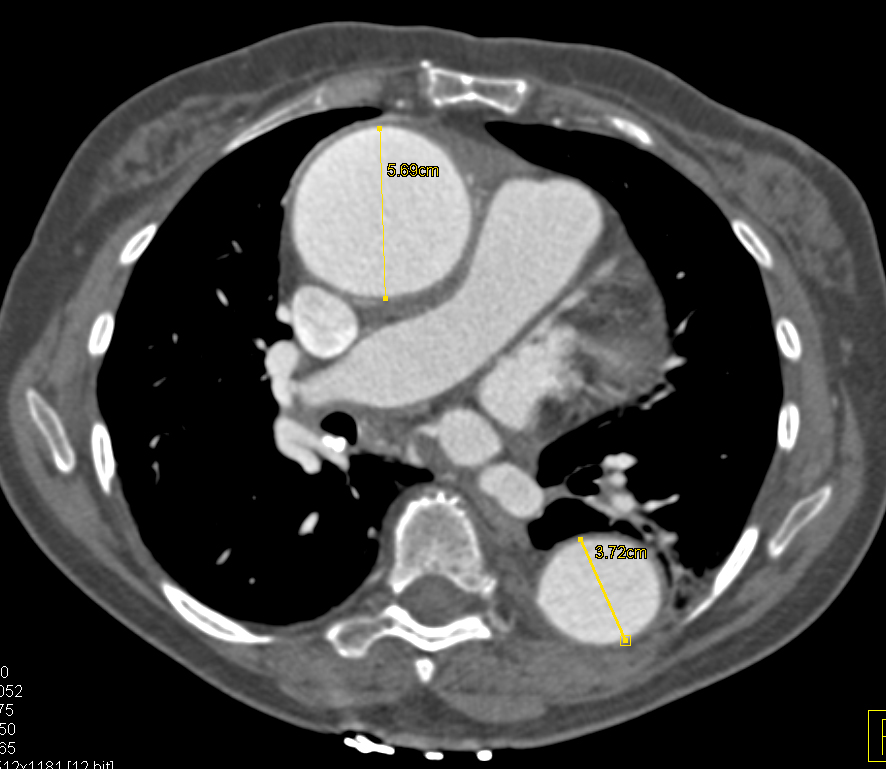

5) In this 30ish year old with chest pain the best dx is?

pseudoaneurysm left ventricle

left ventricle infarction

aortic dissection

right ventricle aneurysm